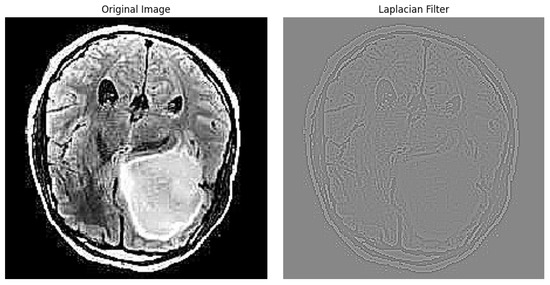

3.3.1. Laplacian Filter

The Laplace filter is one of the many methods used for edge detection.The operator relies on the second derivative to highlight sudden changes in intensity, helping identify important features in the image. The formula for the Laplace filter in image processing is as follows:

2 I ( x , y ) = i = 1 1 j = 1 1 w ( i , j ) · I ( x + i , y + j )

where 2 I ( x , y ) is the intensity of the output pixel ( x , y ) after applying the Laplace filter, I ( x + i , y + j ) represents the intensity of the input pixel at coordinates ( x + i , y + j ) , and  w ( i , j ) are the weights of the Laplacian filter mask. Typically, the weights are defined as follows:

w i , j = 0 1 0 1 4 1 0 1 0

The result of an image after applying the Laplacian filter can be seen in Figure 3.

Figure 3. Edge Detection example using Laplacian Filter.